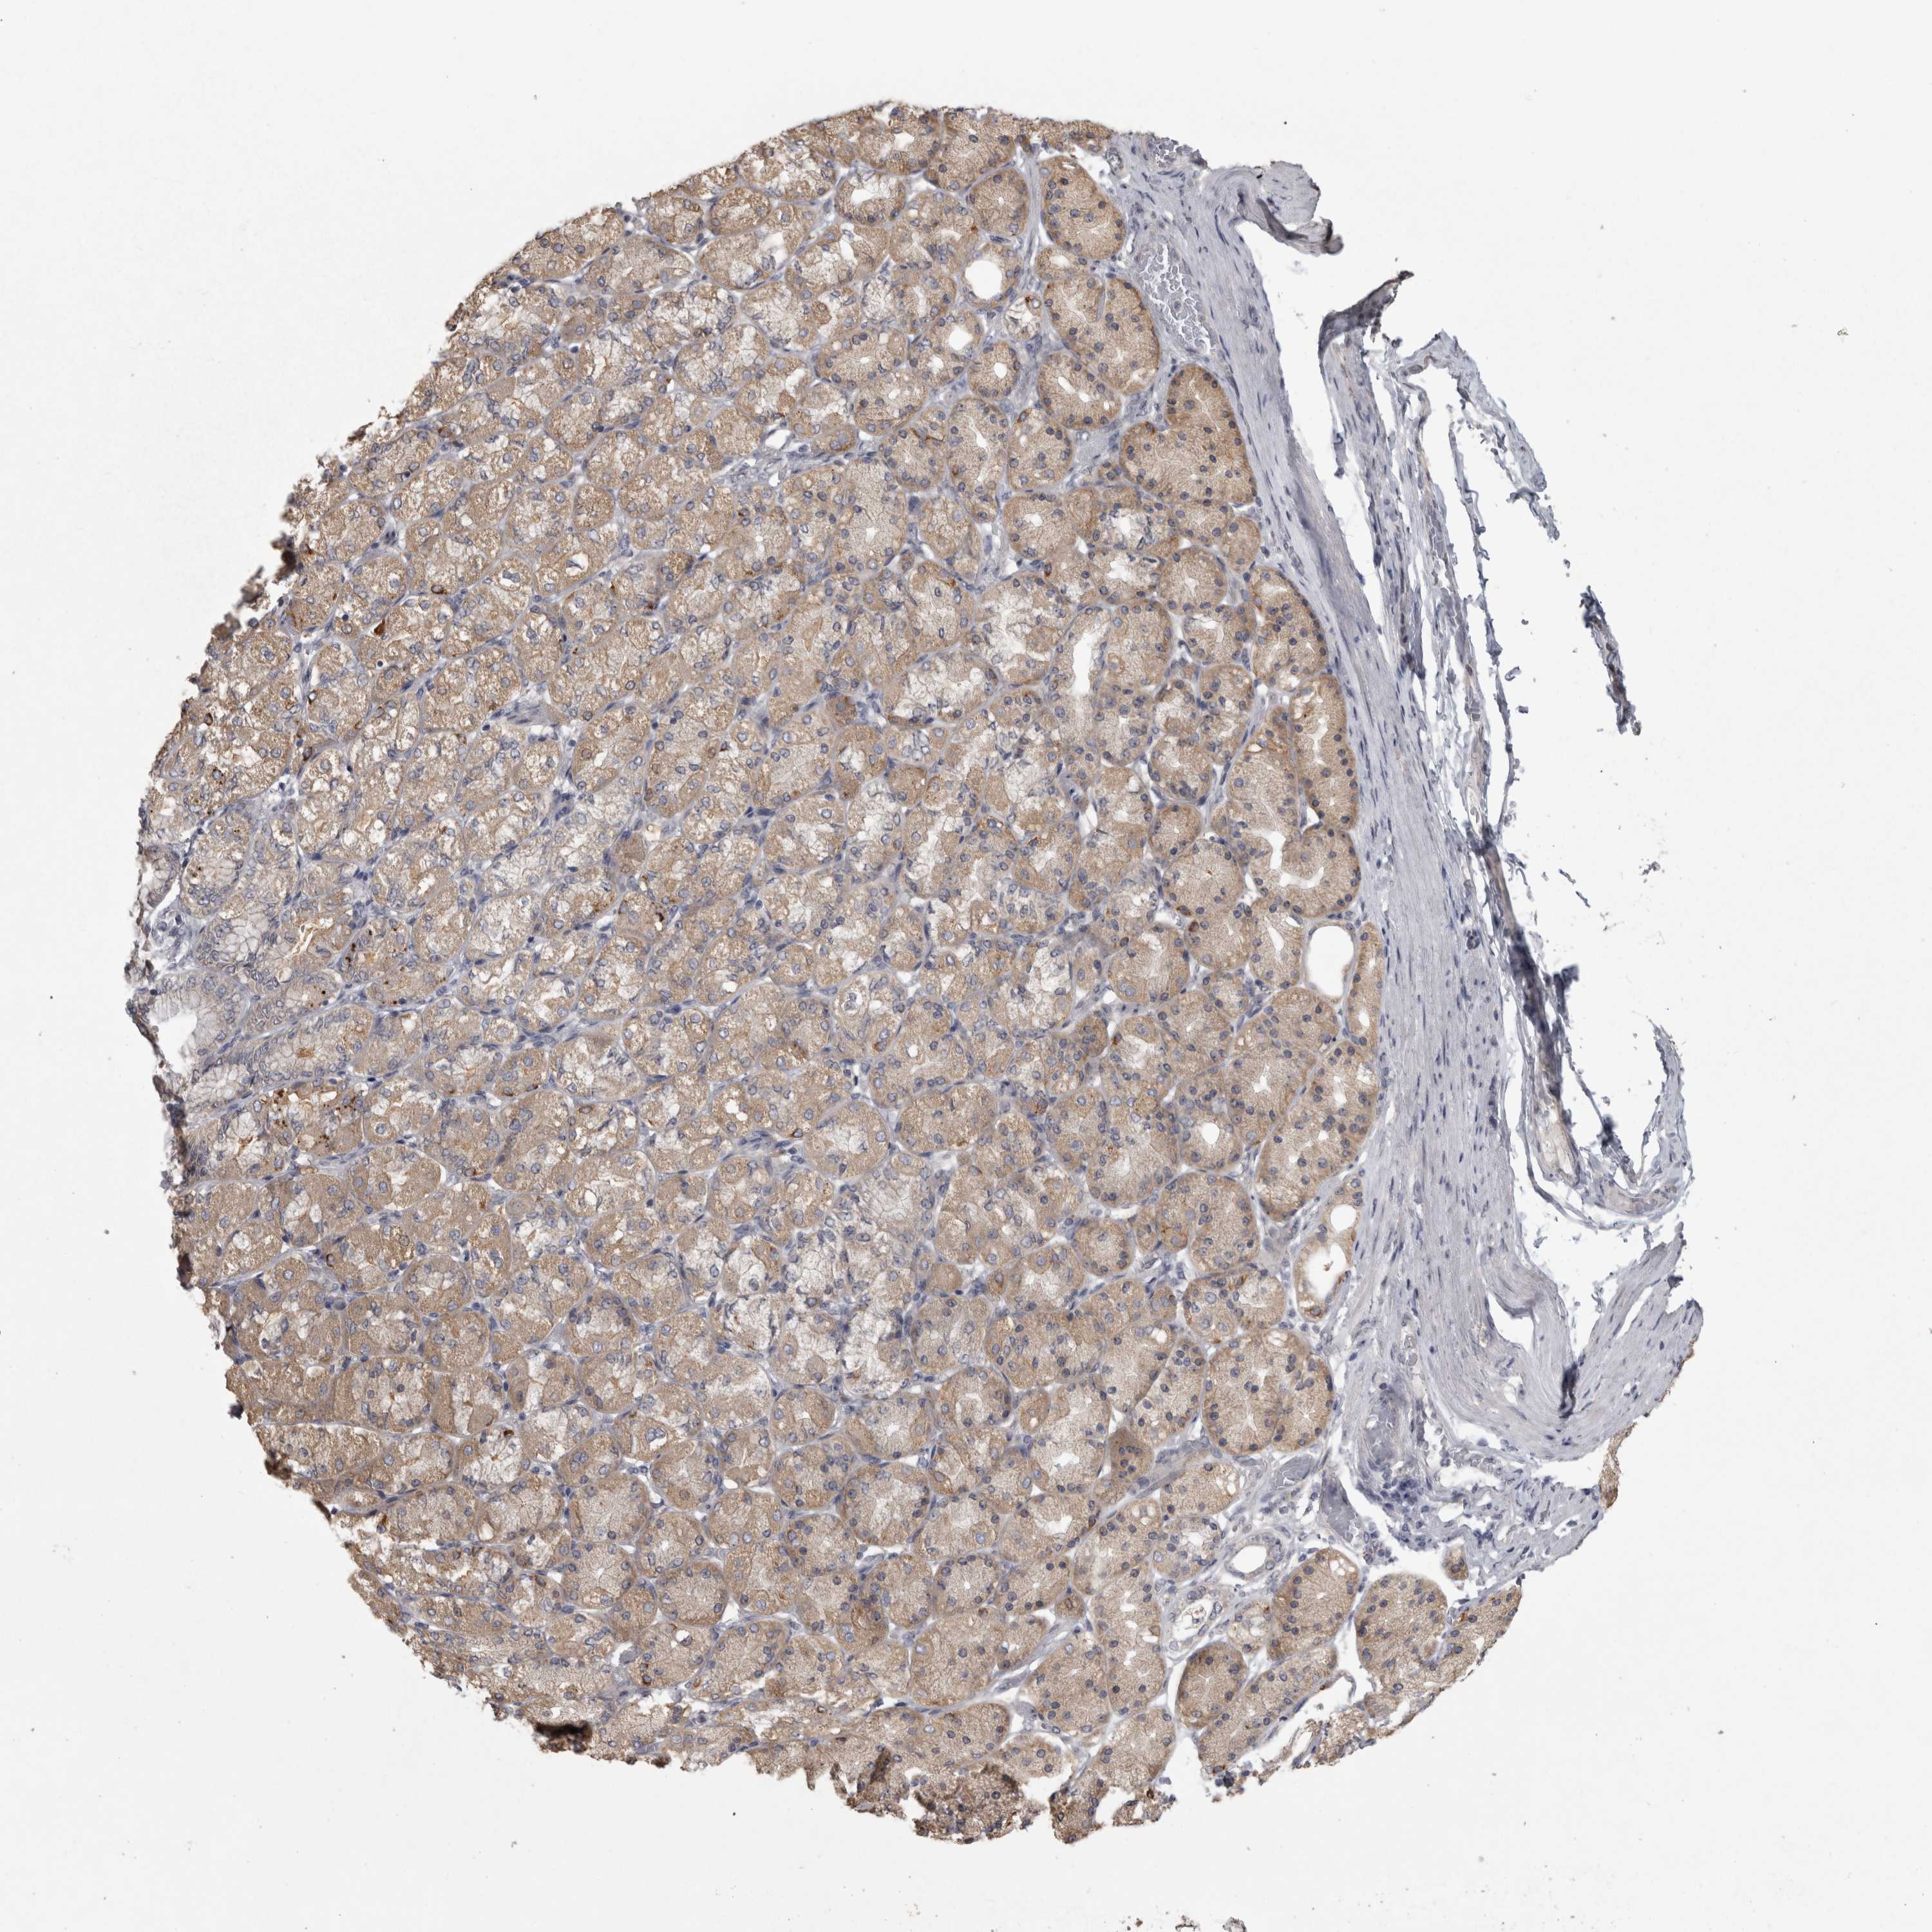

STOMACH CANCER - Protein expressioni

A mouse-over function shows sample information and annotation data. Click on an image to view it in a full screen mode. Samples can be filtered based on level of antibody staining by selecting one or several of the following categories: high, medium, low and not detected. The assay and annotation is described here.

Note that samples used for immunohistochemistry by the Human Protein Atlas do not correspond to samples in the TCGA dataset.

Antibody stainingi

Antibody staining in the annotated cell types in the current human tissue is reported as not detected, low, medium, or high, based on conventional immunohistochemistry profiling in selected tissues. This score is based on the combination of the staining intensity and fraction of stained cells.

Each image is clickable and will lead to virtual microscopy that enables deeper exploration of all samples and also displays staining intensity scores, fraction scores and subcellular localization as well as patient and tissue information for each sample.

Antibody HPA026303

Antibody CAB020822

Staining

High

Medium

Low

Not detected

Intensity

Strong

Moderate

Weak

Negative

Quantity

>75%

75%-25%

<25%

None

Location

Nuclear

Cytoplasmic/membranous

Cytoplasmic/membranous,nuclear

Adenocarcinoma, NOS

Adenocarcinoma, High grade